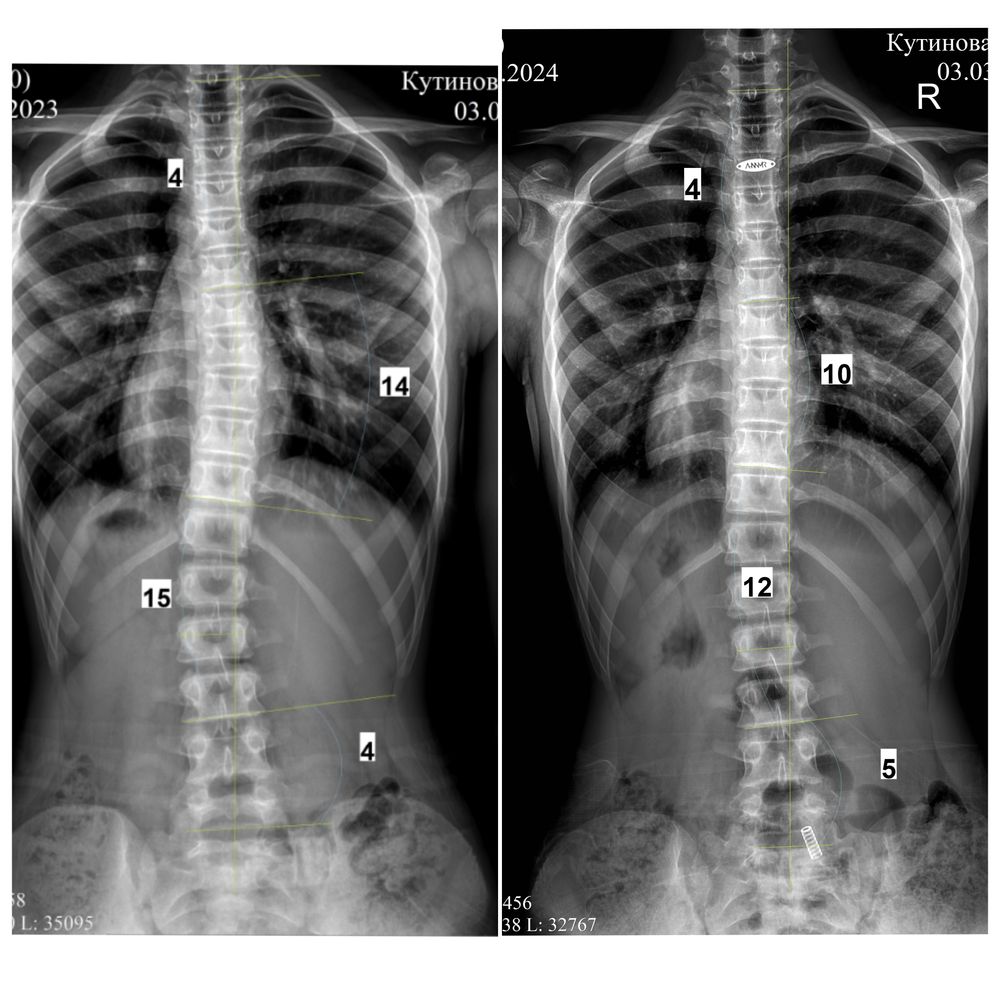

Апдейт от декабря 2024:

Фото без корсета перед выдачей прошлого корсета ( декабрь 2023), и фото без корсета перед заказом нового ( декабрь 2024). Выросла, 177 см,поэтому опять замена (

В декабре 2024 (6,5 лет в корсете, взраст 13 лет 9 мес) нам сказали что делать новый все таки не будут, градусы маленькие, вдруг гиперкоррекция случится) очень было тревожно, но корсет сняли, через три месяца рентген-осмотр 25.02.2025 - пока все ок, еще три месяца гуляем без корсета. Будем делать рентген каждые три месяца, так сейчас самый опасный момент - М нет, рост идет, за три месяца добавила 1 см, итого 177,5 см, через 5 дней 14 лет.